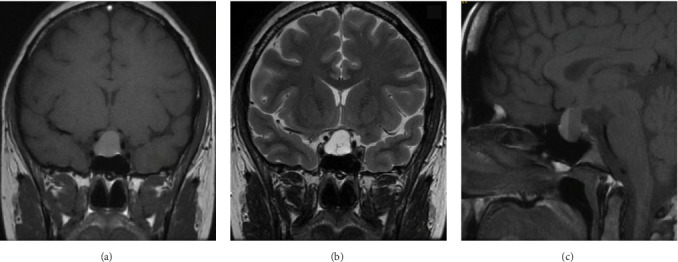

催乳素瘤是垂体腺瘤中最常见的亚型,是导致女性闭经和不孕的主要病因之一。主要的治疗方法需要使用多巴胺激动剂,有效地恢复生育能力。在微泌乳素瘤的病例中,在怀孕期间出现症状性肿瘤扩大的可能性非常低,估计只有2.4%。因此,一旦成功怀孕,停用多巴胺激动剂,并对患者的病情进行持续的临床监测。妊娠期脑垂体中风的发生率极为罕见。我们提出一个病例29岁的患者与微泌乳素瘤,治疗卡麦角林,这是停止在实现怀孕。然而,在妊娠第16周,她出现了持续的头痛和视力下降,表现为左颞偏视。非对比磁共振成像(MRI)显示腺瘤增大,并伴有出血的迹象。她在怀孕26周时被转介到我们医院。卡麦角林治疗恢复,患者耐受良好。剂量增加到每周2毫克,因为双颞偏视没有改善。妊娠35周进行的非对比MRI扫描显示腺瘤尺寸进一步增大,尺寸为17 × 21 × 13 mm,并有瘤内出血的迹象。在妊娠39周进行了有计划的剖宫产手术,没有遇到母胎并发症。由于腺瘤压迫交叉,没有开始母乳喂养。因此,继续使用多巴胺激动剂治疗。在产后随访期间,患者经历了月经周期恢复,催乳素水平正常化,肿瘤大小缩小。最终,诊断确定为微泌乳素瘤,在怀孕期间由于垂体瘤中风而扩大。虽然微泌乳素瘤在妊娠期间通常具有较低的症状性肿瘤生长风险,但本病例强调了警惕的临床监测对迅速发现和处理这种罕见并发症的重要性。这个例子作为一个不常见事件的教育例子-微泌乳素瘤在怀孕期间经历中风。

Prolactinomas are the most prevalent subtype of pituitary adenomas and represent one of the leading etiological factors responsible for amenorrhea and infertility in women. The primary therapeutic approach entails the use of dopamine agonists, which effectively restore fertility. In cases of microprolactinomas, the likelihood of experiencing a symptomatic enlargement of the tumor during pregnancy is exceptionally low, estimated at a mere 2.4%. Consequently, once pregnancy is successfully achieved, the administration of dopamine agonists is discontinued, with ongoing clinical monitoring of the patient's condition. The incidence of pituitary apoplexy during pregnancy is exceedingly rare. We present a case of a 29-year-old patient with microprolactinoma, treated with cabergoline, which was discontinued upon achieving pregnancy. However, at the 16th week of gestation, she presented with persistent headaches and compromised visual acuity, manifesting as left temporal hemianopia. A noncontrast magnetic resonance imaging (MRI) revealed an enlargement of the adenoma, accompanied by evidence of hemorrhage. She was referred to our hospital at 26 weeks of gestation. Cabergoline treatment was reinstated and well tolerated by the patient. Doses were increased to 2 mg per week because bitemporal hemianopia was not improving. A subsequent noncontrast MRI scan performed at 35 weeks of gestation demonstrated a further increase in adenoma size, measuring 17 × 21 × 13 mm, with signs of intratumoral bleeding. A planned cesarean section was performed at 39 weeks of gestation, without encountering maternal-fetal complications. Breastfeeding was not initiated due to the adenoma's compression of the chiasm. Accordingly, dopamine agonist therapy was continued. During the postpartum follow-up, the patient experienced a resumption of menstrual cycles, normalization of prolactin levels, and a reduction in tumor size. Ultimately, the diagnosis was established as a microprolactinoma, which had enlarged during pregnancy due to a pituitary tumor apoplexy. Although microprolactinomas typically carry a low risk of symptomatic tumor growth during pregnancy, this case emphasizes the critical importance of vigilant clinical monitoring to swiftly detect and manage this rare complication. This instance serves as an educational example of an uncommon event-a microprolactinoma experiencing apoplexy during pregnancy.